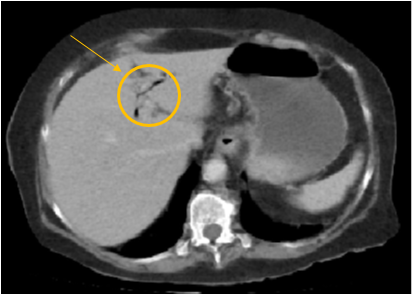

El diagnóstico del IB es un reto. La evaluación de los estudios de imagenología es fundamental, el criterio de diagnóstico imagenológico es la tríada de Rigler que consiste en la presencia de cálculos radiopacos, neumobilia, y distensión de las asas intestinales. Los niveles hidroaéreos y la dilatación de asas intestinales son los hallazgos radiológicos más frecuentemente observados, por otra parte, la tomografía computarizada permite diagnosticar correctamente el íleo biliar con una precisión mucho mayor. 2,3

A continuación, se presentan las imágenes y hallazgos de los diferentes estudios imagenológicos solicitados a la paciente en el proceso de diagnóstico y tratamiento.